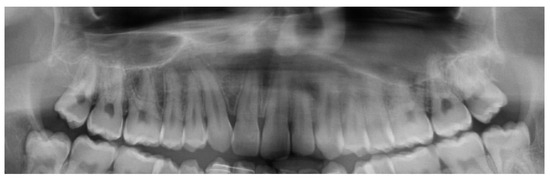

Pre-Surgical Orthodontic Treatment

- Clear aligner technique